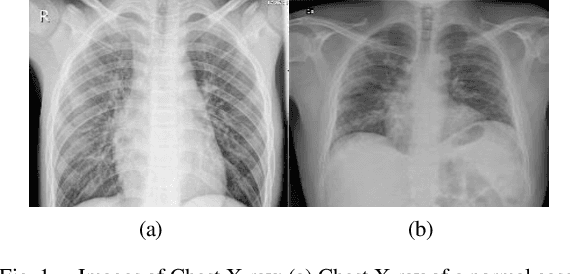

Abstract:Spreading of COVID-19 virus has increased the efforts to provide testing kits. Not only the preparation of these kits had been hard, rare, and expensive but also using them is another issue. Results have shown that these kits take some crucial time to recognize the virus, in addition to the fact that they encounter with 30% loss. In this paper, we have studied the usage of x-ray pictures which are ubiquitous, for the classification of COVID-19 chest Xray images, by the existing convolutional neural networks (CNNs). We intend to train chest x-rays of infected and not infected ones with different CNNs architectures including VGG19, Densnet-121, and Xception. Training these architectures resulted in different accuracies which were much faster and more precise than usual ways of testing.